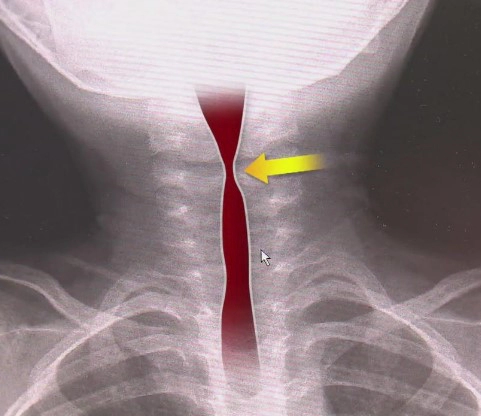

이 증상은 환자가 숨을 들이쉴 때 특히 두드러집니다. 기도의 좁아짐으로 인해 공기의 유입이 제한되고, 이에 따라 호흡 시 '휘파람' 소리를 내게 됩니다. 상태가 심각해지면 숨쉬기가 더욱 힘들어집니다.